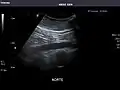

Aorta

Aorta: Visualized portions normal in caliber, 16 x 15 mm.